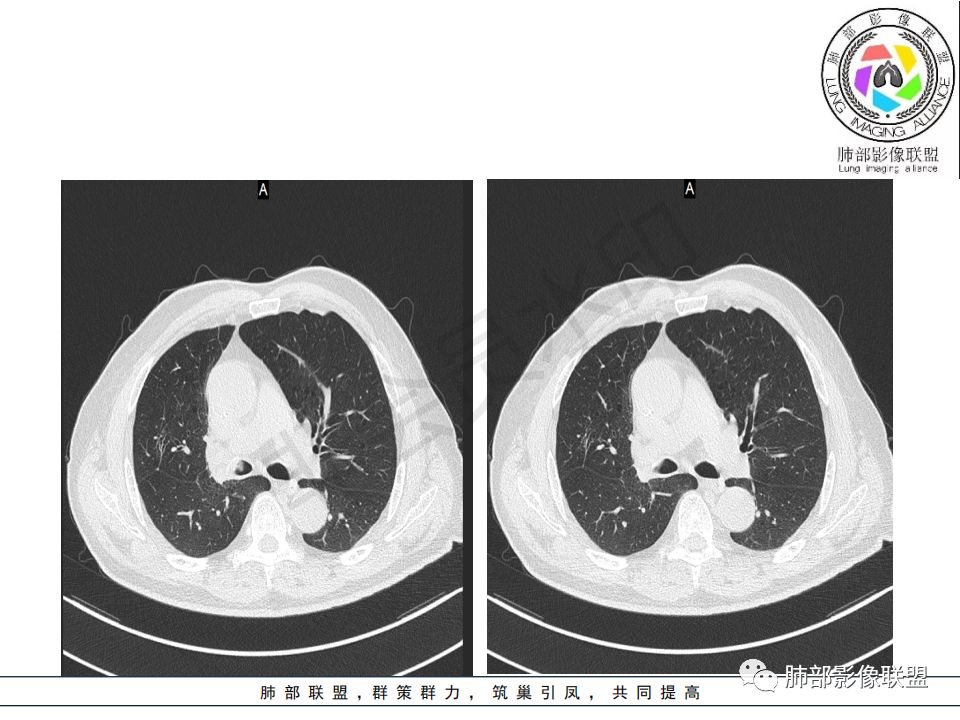

病史:男.77岁,咳嗽1月;干咳,少许白痰,无发热,2013胃癌术后,角蛋白24.65(0-3.07),SCC和proGRP不高;

影像:影像右侧大支气管阻塞,临床没有症状或很轻微,要想到胃腺癌转移;胸壁代偿好,透亮度稍低不明显,慢性过程;34.8-52.5HU,主病灶支气管前壁另有1结节,都做成增强两期了,动脉期较平扫有强化;

诊断:多发,转移,无淋巴结及胸腔积液;

鉴别:原发鳞癌。

晨读:患者老年男性,以咳嗽一月就诊,少量白痰,胸CT:纵隔右移,右肺体积缩小,气管下段管壁可见结节样改变,气管软骨变形,气管下段及右主支气管可见新生物向管壁浸润,并向管腔外生长,右上肺肺不张,但不张边缘可见病灶呈膨胀性生长,可见分叶,增强后强化明显。考虑:肺部恶性病变(鳞癌?)

右肺上叶肿块,边缘光滑,略膨隆,近段支气管堵塞,平扫密度均匀,增强后不均匀强化,其内可见不规则血管和坏死,纵隔淋巴结肿大,老年男性,无感染性病史,综合考虑恶性肿瘤(鳞癌,腺癌),鉴别:OP(一般下叶多见)

1.右肺上叶较大块影,密度不均,轻度强化并见低密度区,所属支气管截断并腔内突入,是符合肺鳞癌的影像学特征和生物学行为的。

2.胃癌常会首先胃旁淋巴结、腹主动脉淋巴结转移,肝脏血行转移,以及双肺多发转移,本例孤立右肺上叶病灶巨大,多有不符。